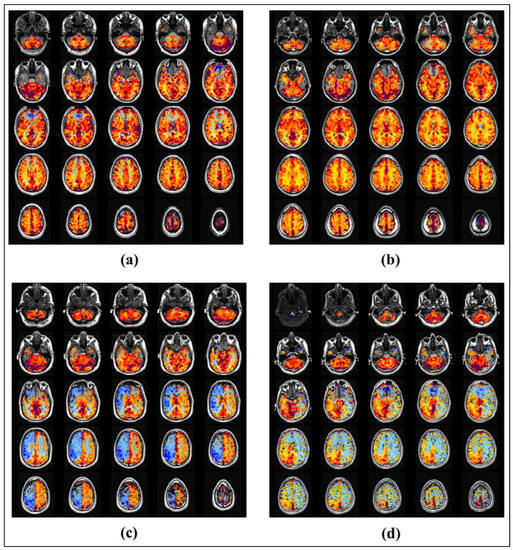

3.1. Data Analysis and Pre-Processing